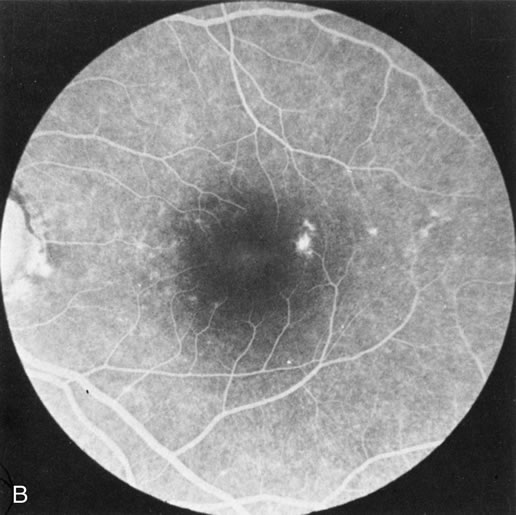

Dye leakage in RP may occur from the retinal vessels or at the level of the retinal pigment epithelium (Fig. 1B).2–4 The leakage may be seen in the macula and posterior pole, along the vascular arcades in the distribution of the radial peripapillary capillaries, and in the periphery (where an exudative vasculopathy resembling Coats' disease is suggested).